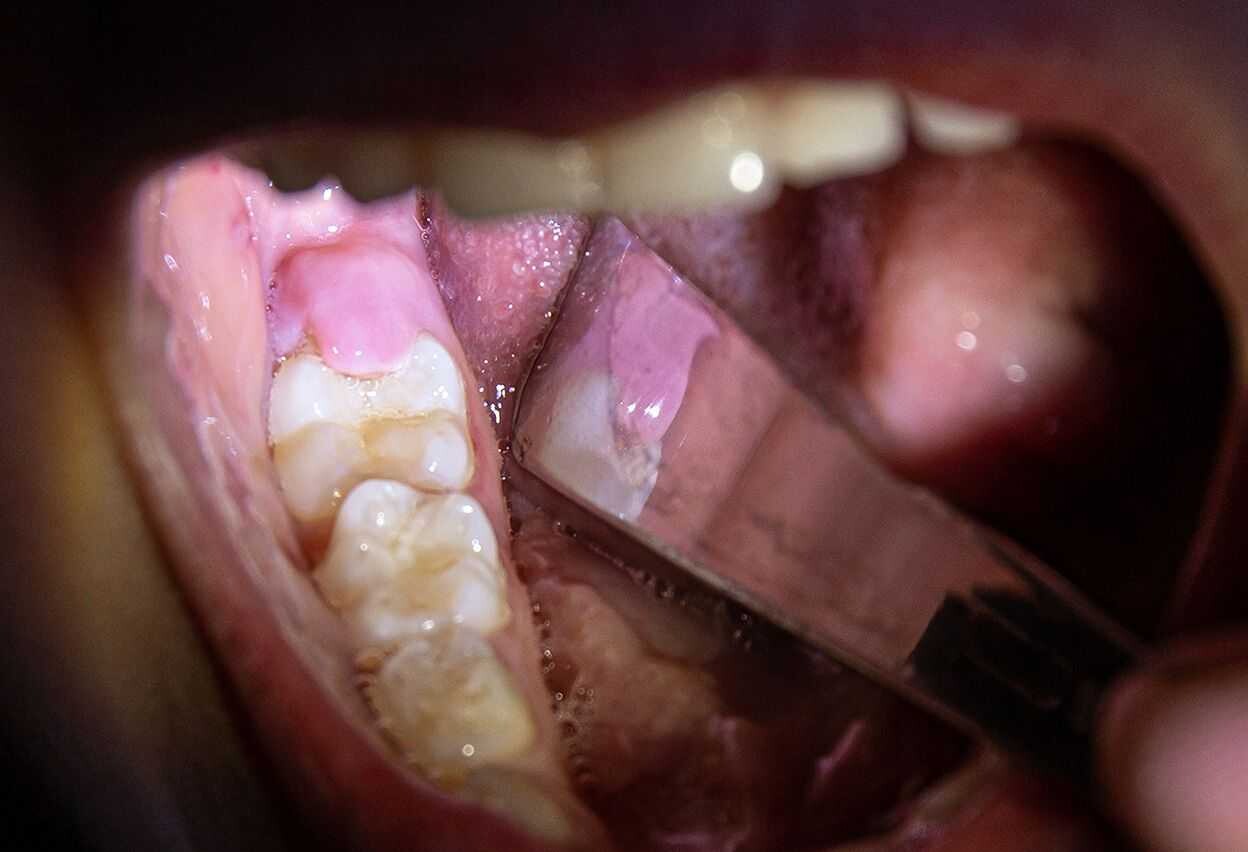

Enamel Damage can result in black teeth

Decay or cavities are the most common reason for teeth turning black. When the pulp becomes infected, the black color begins inside the tooth and works its way to the surface. The black appearance often starts as a few dark spots, but when left untreated, the whole tooth can turn black. Turning black is usually a gradual transformation that begins with brown or gray spots or small dots of black near the gum line.

An injury to the mouth can damage the tooth so badly that it dies, in which case the tooth may also turn black.

Tartar and Stains

Tartar that develops on the outside of the molars or inside the front teeth can build up stains and erode holes in the teeth and make them look black.